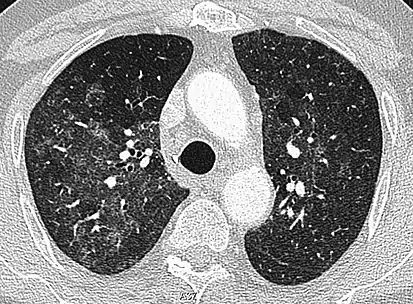

CT image showing diffuse GGOs throughout both lungs. An abscess is also noted in the right lung (screen left). - Adenocarcinoma in situ of the lung

The diffuse pattern typically refers to GGOs in multiple lobes of one or both lungs. Broadly, a diffuse pattern of GGO can be caused by displacement of air with fluid, inflammatory debris, or fibrosis. Cardiogenic pulmonary edema and ARDS are common causes of a fluid-filled lung. Diffuse alveolar hemorrhage is a rarer cause of diffuse GGO seen in some types of vasculitis, autoimmune conditions, and bleeding disorders.[6]

Inflammation and fibrosis can also cause diffuse GGOs. Pneumocystis pneumonia, an infection typically seen in immunocompromised (e.g. patients with AIDS) or immunosuppressed individuals, is a classic cause of diffuse GGOs. Many viral pneumonias and idiopathic interstitial pneumonias can also lead to a diffuse GGO pattern. Radiation pneumonitis, a side effect of pulmonary radiation therapy, can lead to pulmonary fibrosis and diffuse GGOs.[6]